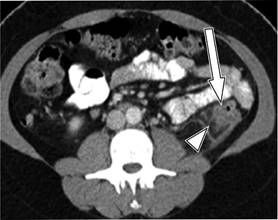

El estadio de la enfermedad en pacientes con diverticulitis a menudo se determina mediante el sistema de clasificación de Hinchey modificada por Wasvary (1999) y los hallazgos tomográficos por Kaiser a los que se incorporan los resultados de imagen (Cuadro 1 y Figura 1),16 los cuales comprenden desde el estadio 0 hasta el IV, en los que el estadio 0 (Figura 2) nos habla de una diverticulitis clínicamente moderada. El estadio I se divide en dos el IA (Figura 3) que se refiere a la inflamación pericólica limitada sin absceso y el estadio IB (Figura 4) en el que además de inflamación hay absceso adyacente a la zona de inflamación. En el estadio II (Figura 5) se encuentra el absceso pélvico, retroperitoneal o a distancia. En el estadio III (Figura 6) evoluciona a peritonitis generalizada sin comunicación a la luz intestinal y en el estadio IV hay peritonitis fecaloide con comunicación a la luz intestinal.17,18

Figura 4: Diverticulitis grado IB: TC muestra engrosamiento de la pared del colon sigmoides (flecha) con pequeño absceso pericólico (cabeza de flecha) y cambios en la grasa pericólica.